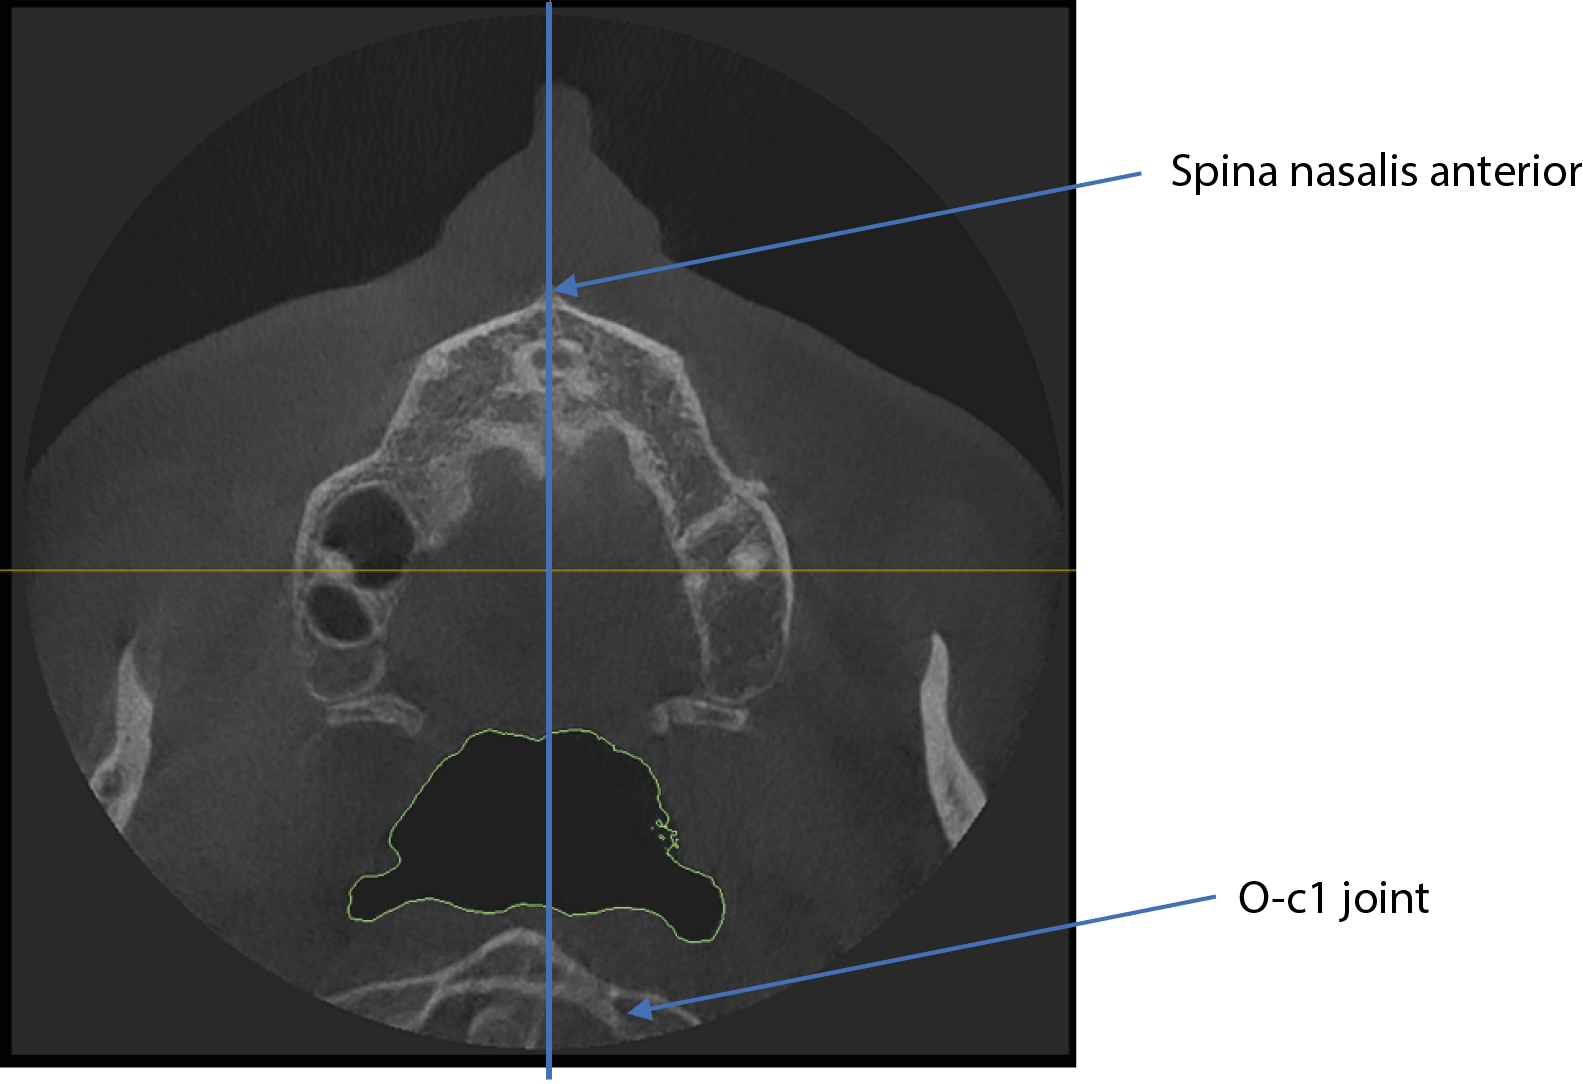

Abnormality in the position of the O-C1 joint

In addition to airway volume, the study investigated the correlation between lower airway capacity, dental abnormalities, and postural problems at a vertebral level. The deviation of the O-C1 (atlanto-occipital) joint was measured by automatically drawing a sagittal midline-using the spina nasalis and the sutura palatina media as reference points. Any displacement of the O-C1 spinous process relative to this midline was used to assess vertebral asymmetry. The methodology is illustrated in Figure 6.